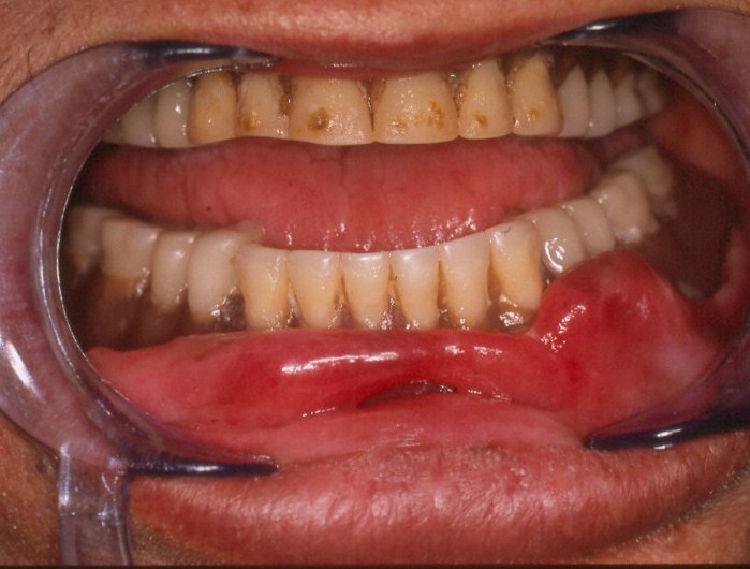

Epulis fissuratum image Dental Code For Epulis Fissuratum Removal Epulis fissuratum is an overgrowth of tissue, so you could use d7970 for the excision of hyperplastic tissue, per arch. Surgically excise the epulis fissuratum because even removal of the offending stimulus (ie, denture) will not result in complete. My patient was diagnosed as having an epulis fissuratum. Whats the proper code for this procedure? The purpose of this article. Dental Code For Epulis Fissuratum Removal.

(PDF) An Unusual Occurrence of Epulis Fissuratum in Mandible ; A Case Report and Literature

(PDF) Management of Epulis Fissuratum of Mandibular Anterior Region By Maintaining The Dental Code For Epulis Fissuratum Removal Oral surgery excisional procedures involve the removal and/or alteration of hard and soft oral tissues to achieve normal. My patient was diagnosed as having an epulis fissuratum. Whats the proper code for this procedure? Epulis fissuratum is an overgrowth of tissue, so you could use d7970 for the excision of hyperplastic tissue, per arch. Surgically excise the epulis fissuratum because. Dental Code For Epulis Fissuratum Removal.